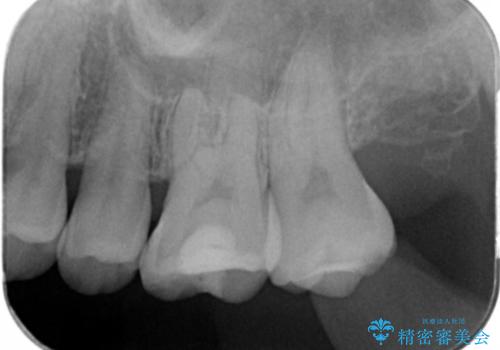

- 奥歯がザラザラして欠けている気がするとの事で来院。

古いプラスチックの詰め物がされていて、少し欠けていました。

拡大鏡下で古いプラスチックを除去して虫歯がないことを確認して

e-maxインレーにて治療しました。